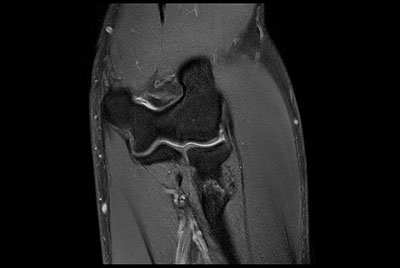

Knee ACL repair